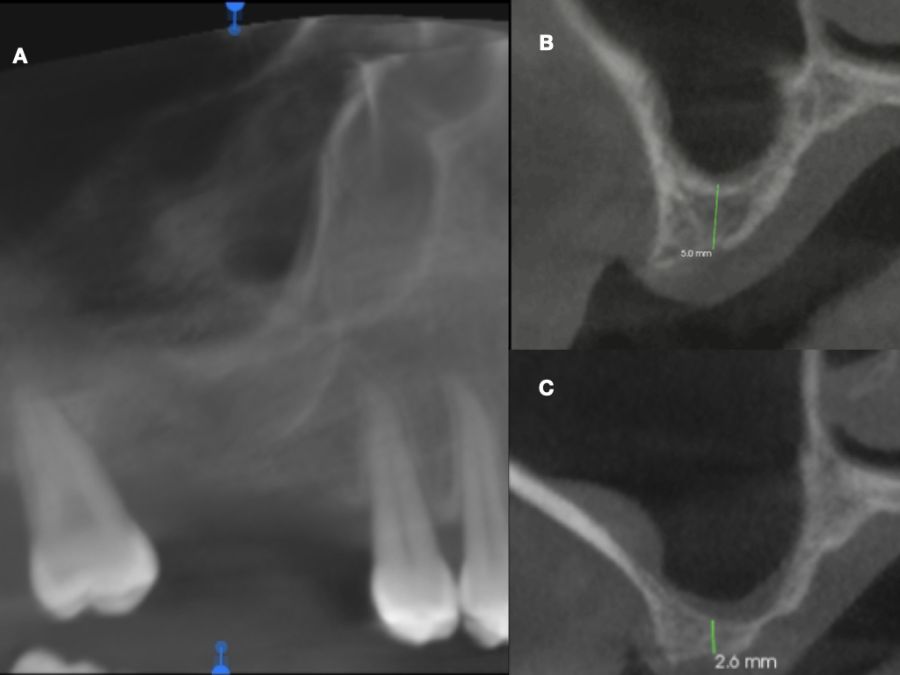

En la historia clínica, no se evidenciaron antecedentes médico-quirúrgicos de interés, alergias medicamentosas conocidas ni hábitos nocivos. A la exploración intraoral, se apreciaron las ausencias de 1.6 y 1.7 y la presencia del 1.8 y 4.8 (Figura 1). En la exploración radiográfica mediante escáner de haz cónico (CBCT) se apreció una altura residual de 5,0 mm en 1.6, donde se podría colocar un implante simultáneo, y de 2,6 mm en la zona del 1.7, dificultando la colocación de un implante de manera simultánea a la elevación de seno de acceso lateral (Figura 2).

Seis meses tras la cirugía de elevación de seno maxilar se realizó la reentrada para la colocación de implantes. Se obtuvo una biopsia de tejido óseo de 3 x 7 mm mediante trefina y se solicitó un análisis histomorfométrico, obteniendo un 30,56% de hueso vital (Figura 7). Tras la muestra para la biopsia se colocaron dos implantes bone level Naturactis de ETK® (ETK Implants S.L, Sant Boi de Llobregat, España) con un torque de inserción de 35 Ncm, comprobándose su correcta colocación en el postoperatorio inmediato mediante una radiografía periapical (Figura 8). Seis meses tras la colocación de los implantes la paciente pudo acudir a realizarse la segunda fase para colocar pilares de cicatrización, y mediante un CBCT de comprobación se valoró la altura ósea final, teniendo un incremento de 4,2 mm en la zona del 1.6, y de 6,1 mm en la zona del 1.7 (Figura 9).